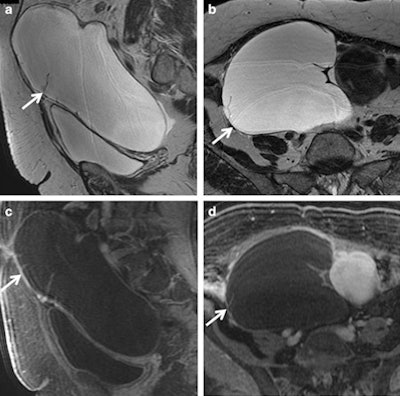

In their research, Foti and colleagues found morphological characteristics of adnexal masses range from cystic (both unilocular and multilocular), to complex (cystic and solid), to predominantly solid.

The most predictive characteristics of malignancy are vegetations in a cystic lesion, presence of ascites, a maximal diameter greater than 6 cm, and necrosis in a solid lesion. Other research suggests malignancy in the demonstration of solid, solid/cystic enhancing masses (greater than 4 cm in maximum diameter) with papillary projections, and irregular thick wall and septa (greater than 3 mm) into a cystic lesion, as well as a heterogeneous and early enhancement pattern.